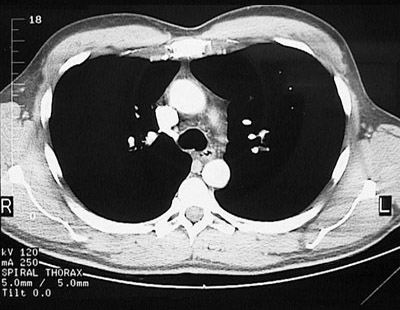

[T5-T6] This is a normal chest CT scan demonstrating the right lung and left lung and pectoralis major muscle and superior vena cava and aortic root and sternum and descending aorta and esophagus and trachea and subscapularis muscle and spine of scapula and infraspinatus muscle and trapezius muscle and rhomboid major & minor muscle and transversospinal muscle in the upper chest.